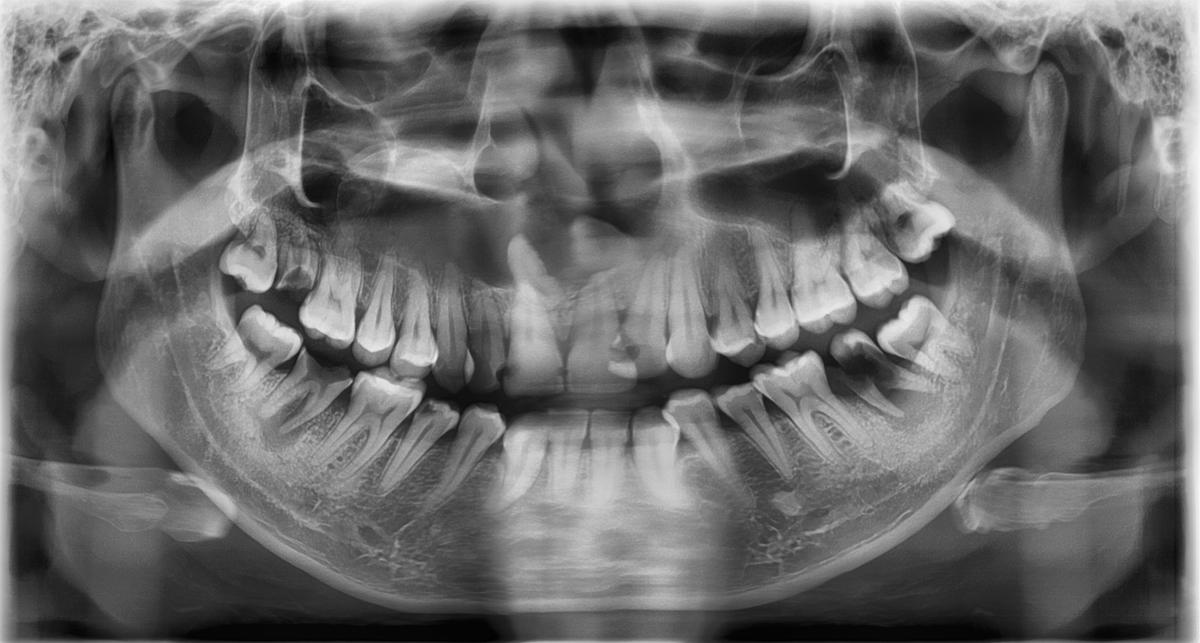

L'examen clinique et radiographique

Lors de l’examen clinique, le médecin examinera attentivement la zone affectée pour déterminer si elle est enflée ou sensible au toucher. Il peut également prescrire une radiographie panoramique pour obtenir une vue complète du crâne et de la mâchoire afin de confirmer le diagnostic.